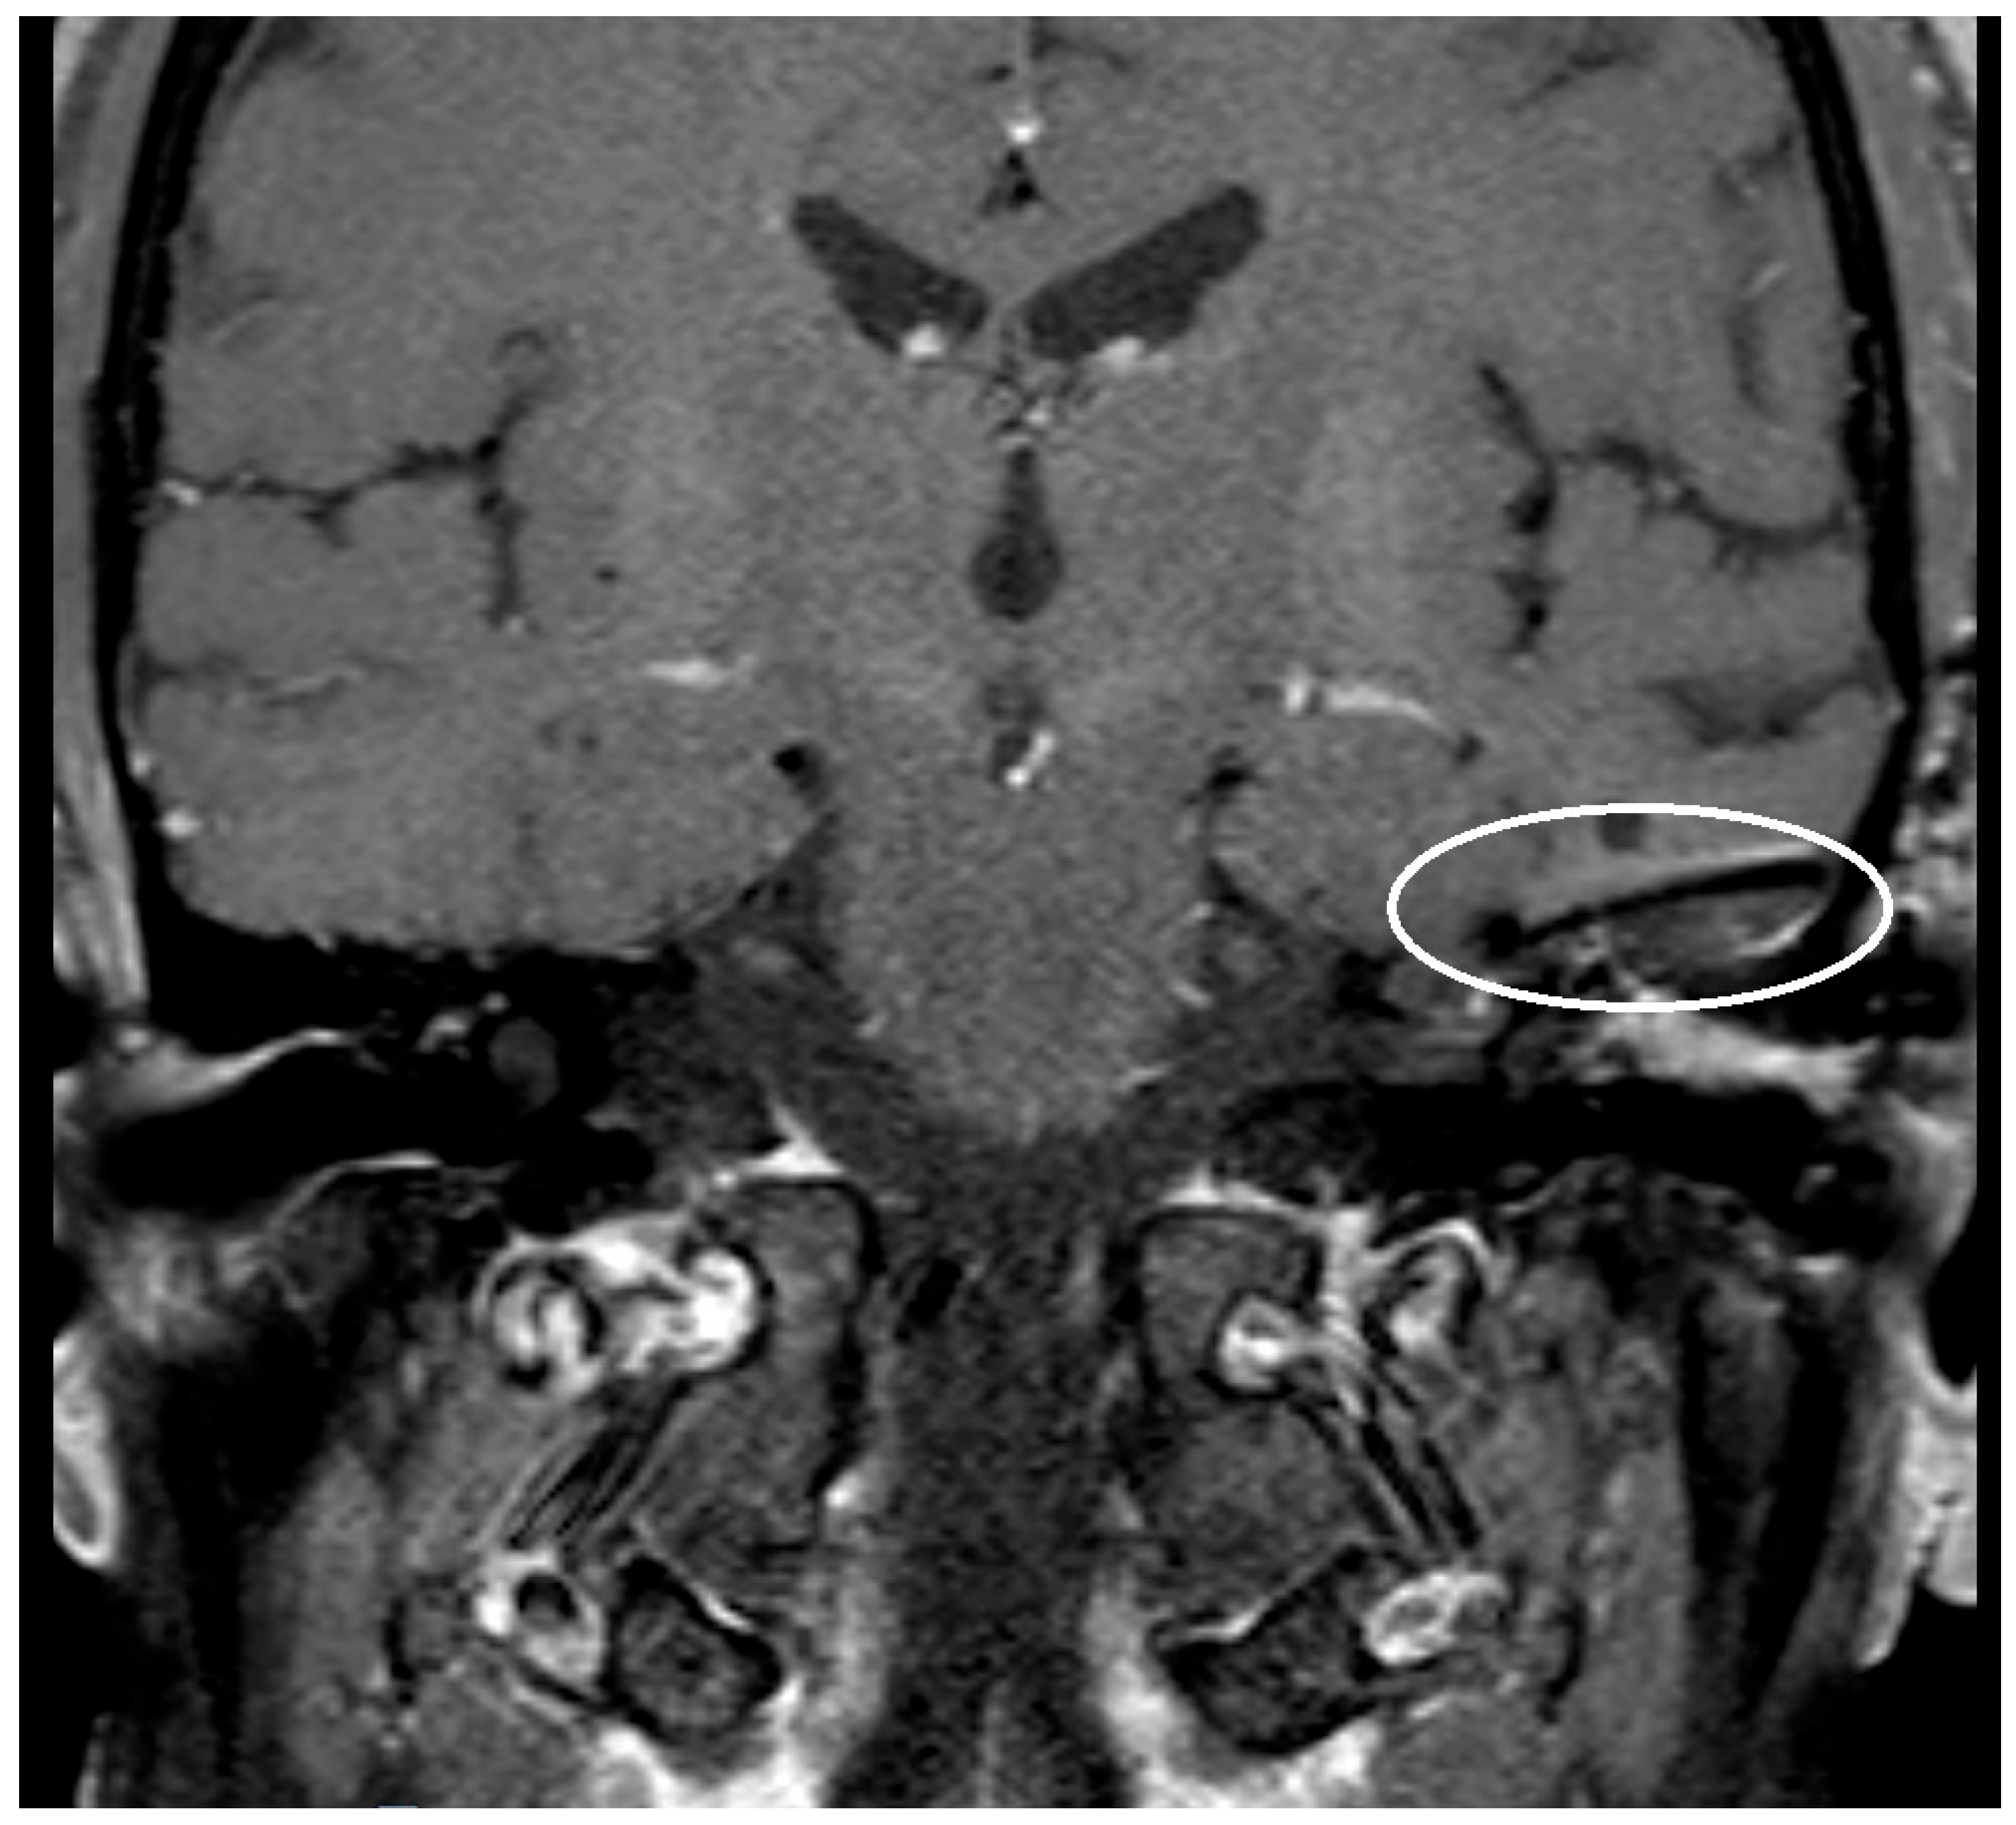

Figure 1. T1 fat-suppressed-Sequence post Gadolinium with artifact after implantation of a titanium mesh at the left-sided skull base, see white ellipsis.

An artifact was detected in all MRI examinations (see Figure 1, Figure 2 and Figure 3).

The artifact measurements firstly done in T1- or T2-sequence showed an average artifact of 3,1 mm for PORP, 4,7 mm for TORP and 3,6 mm for meshes (see Figure 4, Figure 5 and Figure 6). The overall average artifact was 3,8 mm.